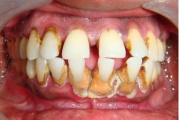

Krooniline parodontiit

Krooniline parodontiit on mikroobide poolt põhjustatud hammaste tugikudede põletik, mille tulemusena tekib progresseeruv alveolaarluu (nähtav röntgenograamil) ja periodontaalligamendi destruktsioon, igemetaskute moodustumine, igeme retsessioon või mõlemad kahjustused kombineeritult. Loe edasi »

- igemed veritsevad (19)

- igemed punetavad (21)

- ige on paistes (mädapunn)

- igemed on tursunud/vohavad (17)

- igemepiir on taandunud (3)

- luu destruktsioon (5)

- hammaste asukoha muutus (5)

- vahed hammaste vahel (5)

- igemetaskust eritub mäda (3)